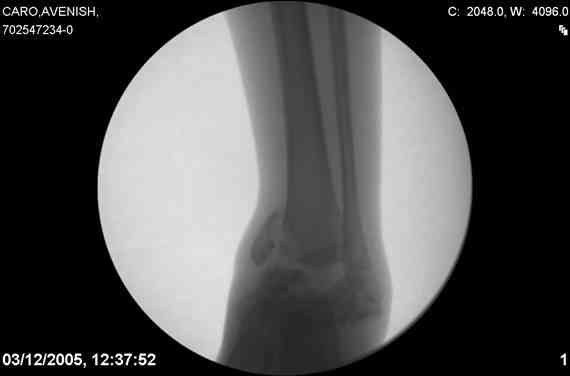

ya by popytalsya sobrat talus anatomichno,seichas pozdno operirovat

iz za oteka,po etomy distrakziya apparatom budet optmalna.Posyalu vam

podobyai moi sluchai.